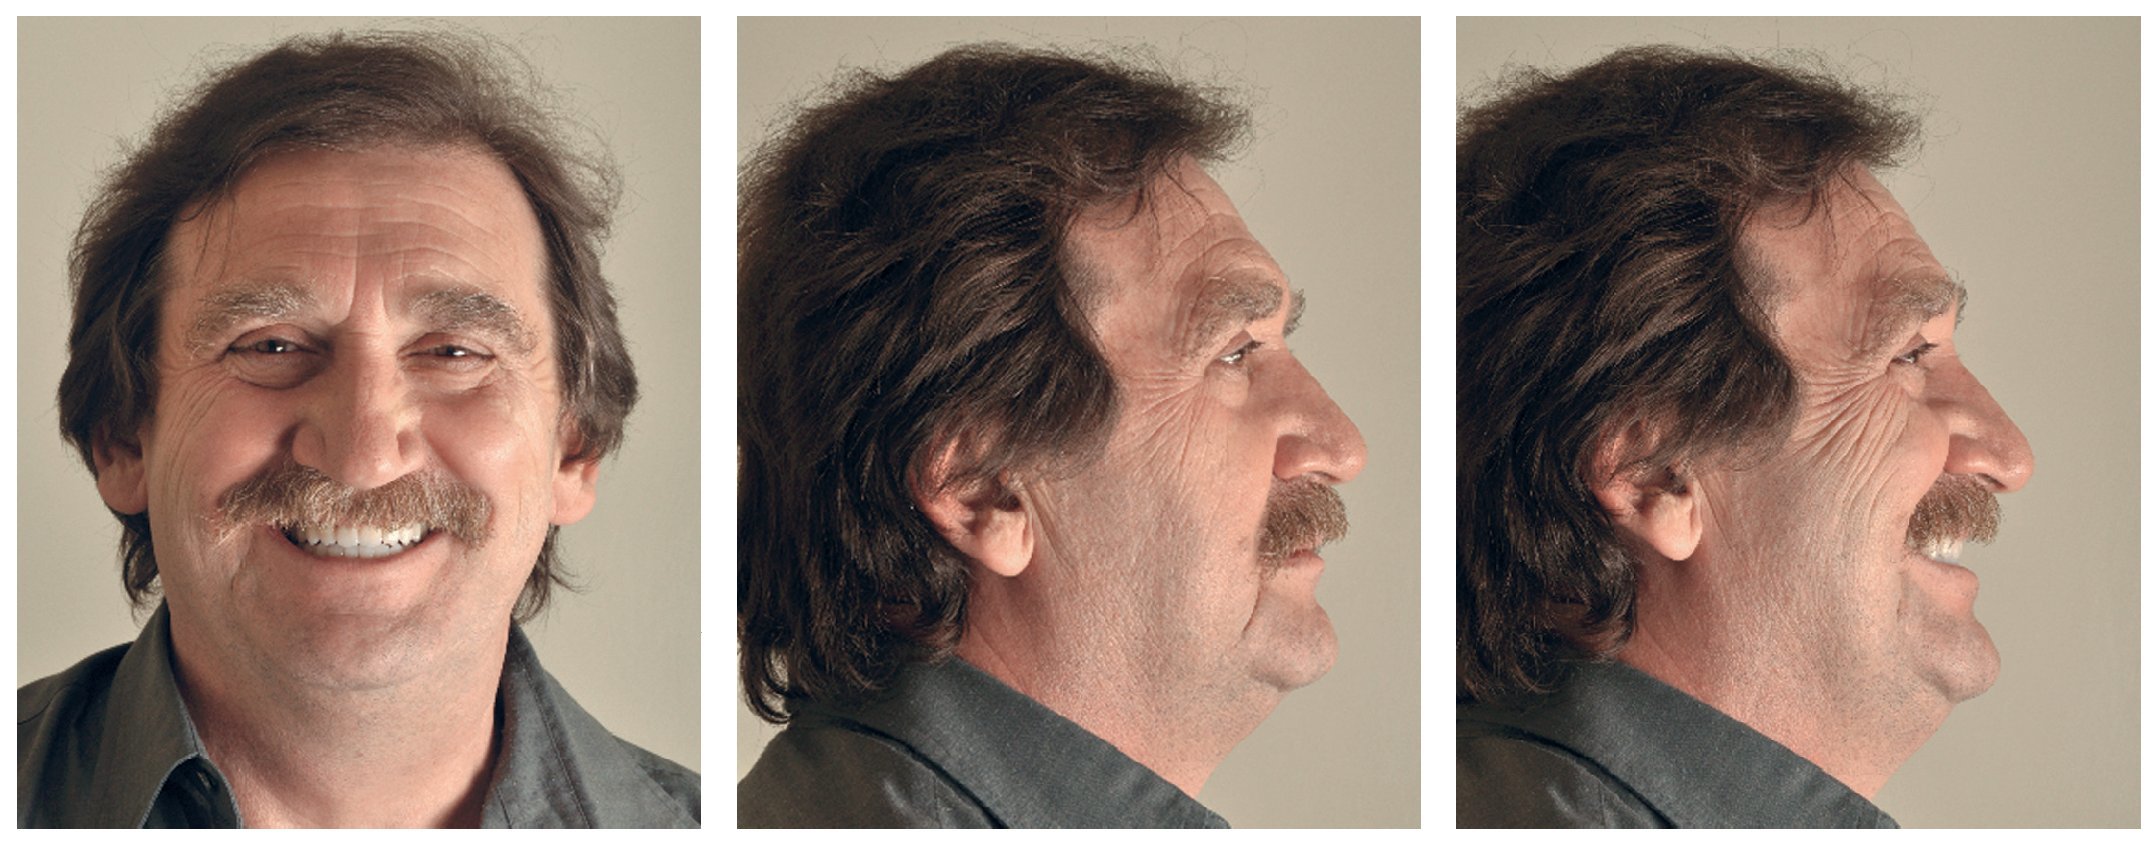

Para la rehabilitación definitiva del paciente (figs. 116 a 124) deben comprobarse de nuevo todos los aspectos de la sesión anterior y debe procederse a la cementación de las prótesis. Son indispensables controles de seguimiento a corto plazo (al cabo de 1, 3 y 5 semanas) para el ajuste óptimo de la oclusión y la comprobación de la higiene oral con una prótesis que habitualmente ofrece aberturas de acceso periimplantares más estrechas que una prótesis provisional. Tres y seis meses después de la finalización del tratamiento se deben realizar controles clínicos, y una vez al año deberían llevarse a cabo sendos controles clínico y otro radiológico.

Figs. 122 a 124. La situación final extraoral.